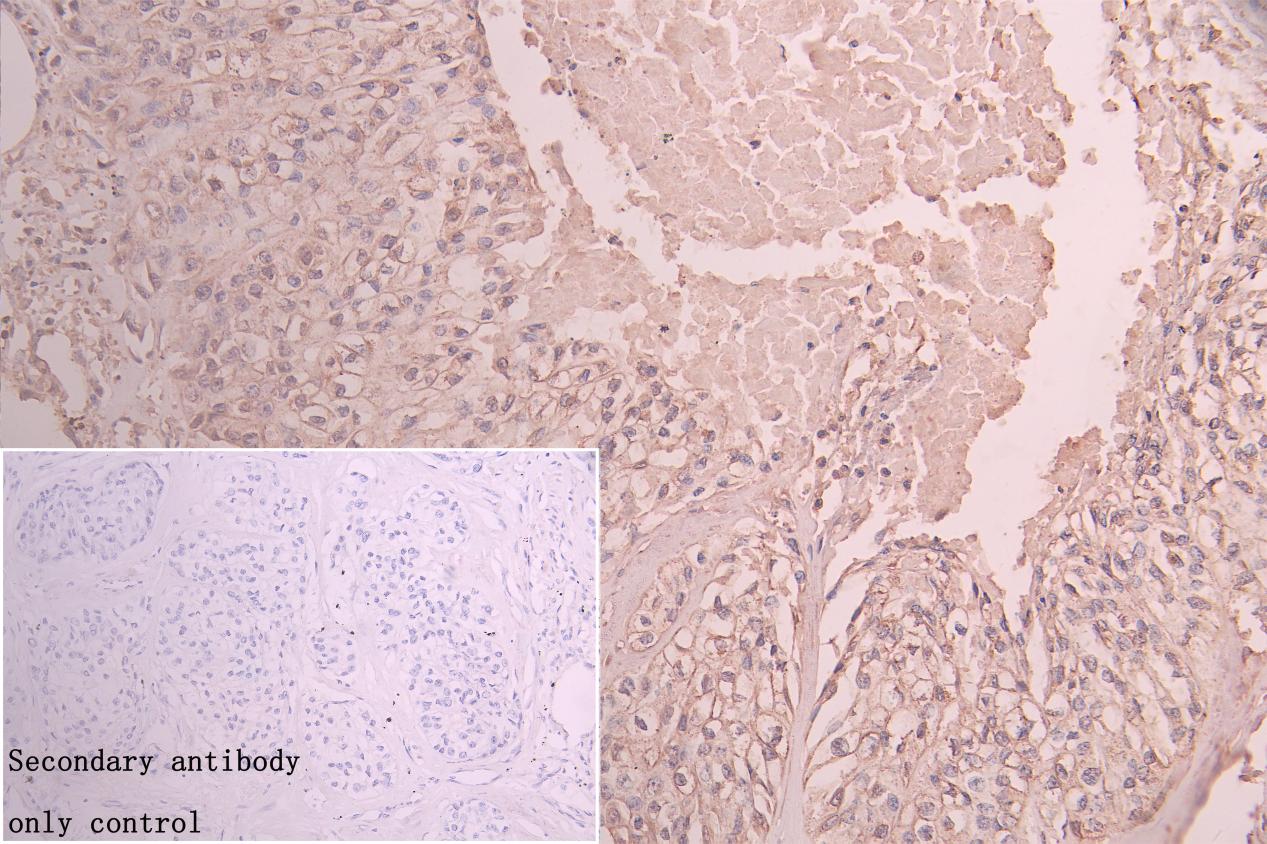

IHC image of CSB-PA873612LA01HU diluted at 1:75 and staining in paraffin-embedded human pancreatic cancer performed on a Leica BondTM system. After dewaxing and hydration, antigen retrieval was mediated by high pressure in a citrate buffer (pH 6.0). Section was blocked with 10% normal goat serum 30min at RT. Then primary antibody (1% BSA) was incubated at 4°C overnight. The primary is detected by a Goat anti-rabbit polymer IgG labeled by HRP and visualized using 0.05% DAB. Secondary antibody only control: uses 1% BSA instead of primary antibody